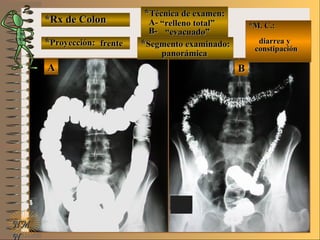

C-C-

**Segmento examinado:Segmento examinado:

*M. C.:*M. C.:

sin clínicasin clínica

NMNM

BBAA CC

E ME M

UNTUNT frentefrente

““relleno total”relleno total”

““mucosografía”mucosografía”

““doble contraste”doble contraste”

panorámicapanorámica

A-A-El examen es normal o patológico?El examen es normal o patológico?

Examen normal de estómago panorámico conExamen normal de estómago panorámico con

técnicas de : A- relleno total, B- mucosografíatécnicas de : A- relleno total, B- mucosografía

(tiene por objetivo reconocer el relieve interno(tiene por objetivo reconocer el relieve interno

grueso = a pliegues) y C- doble contraste (relievegrueso = a pliegues) y C- doble contraste (relieve

interno fino) en proyección de frenteinterno fino) en proyección de frente

B-B-Puede describir la o las imágenesPuede describir la o las imágenes

**OpciónOpción

de volverde volver